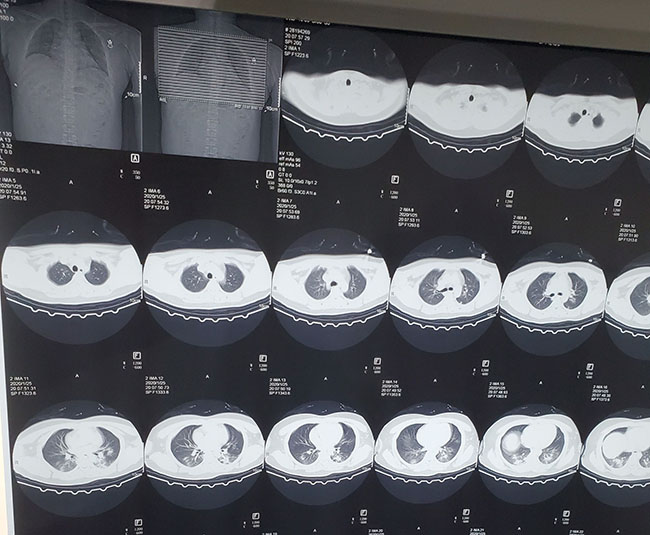

Chụp CT ngực của một người đàn ông 34 tuổi bị coronavirus ở Trung Quốc. Một nửa trong số những bệnh nhân nhiễm Covid-19 trong 2 ngày đầu tiên không có những triệu chứng rõ rệt ở phổi. (Ảnh: Internewscast)